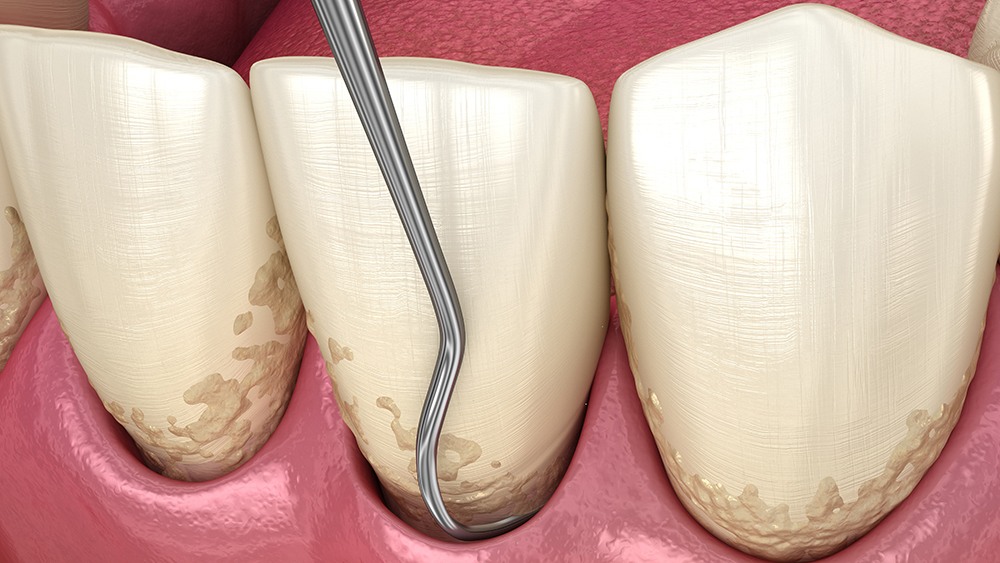

またお口のクリーニングでは、歯にこびりついた歯石を丁寧に除去。治療終了後は再度詳しい検査を行い、治療前の検査結果と比較して歯周病が改善しているかを確認します。

歯石やプラーク(歯垢)

を取り除く

歯周病の原因となる歯石やプラーク(歯垢)を、専用の器具を使って取り除きます。